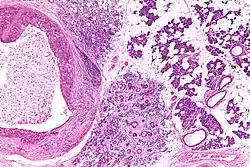

Their histologic appearance is similar to ductal breast carcinoma.

Intermed. mag.